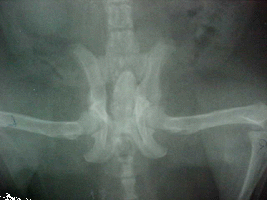

Pelvic X-ray showing poor bone density Pevic X-ray showing good bone density

Poor Bone Density Good Bone Density

Malnutrition, poor diet (green bean's, pea's, lettuce); X-rays show very little bone mass or muscle, bones thin and brittle like egg shell, severely deformed legs.

Treatment: Morning: 1/8 tsp. Rep-Cal powder, 1/2 squirt liquid taurine, pinch Echinacea (first three weeks to build up his immune system), 1/3 cup thawed frozen veggies, 10 Cheerios or soy cereal. Lunch: 1/2 cc Pet Tinic (for 4 weeks), 1/8 - 1/4 tsp. colostrum, 1/8 tsp. whey powder, 1 tbsp. skunk mixture, sardines, or salmon; 1 tsp. low fat yogurt. 3:00 PM: Vitamin K, fresh vegetables, 1/8 tsp. Vitamin C, tofu or raw oats. Supper: 1/8 tsp. Rep-Cal., dab of Feliobite II, 1/8 tsp. whey powder, fresh veggies, chicken or Skunk mixture, 1 tsp. low fat yogurt, blueberry, apple or pear (small amount). Nighttime snack: four small pieces of Bil-Jack dog food. Used Reptile Light [UV+ lamp] for 15 minutes per day while eating. X-rays in 58 days show remarkable regrowth in bones. Still badly deformed. Added 1/4 tsp. Synovi-MSM and B-complex to diet twice daily, dropped the whey to 1/8 tsp. daily.